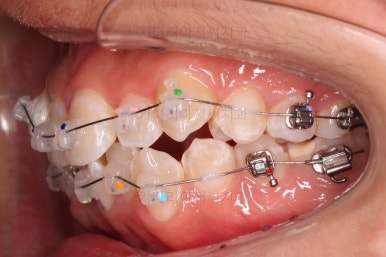

초진 시 입안의 모습입니다.

앞니가 많이 삐뚤고, 송곳니가 부각되어 덧니처럼 보이네요.

장치를 처음 부착한 모습입니다.

이번 환자분이 선택하신 장치는 데이몬 클리어라고 하는 자가결찰 세라믹 장치인데요.

흔히들 아시는 클리피씨 장치 등등에 비해 현존하는 브라켓 중에 가장 심미적인 장치입니다.

가지런하게 하는 단계를 거친 뒤,당기기 과정에 들어가는데요.

이 과정에서 입이 들어가는 양, 중앙선, 기울기, 앞니 각도 등등 많은 것을 신경써서 당기기를 해주는데요.

이 때 필요한 것이 미니스크류 입니다.

예전과는 다르게 미니스크류를 이용해서 좀 더 정교하고 고난이도의 치료가 가능해지게 된거죠.